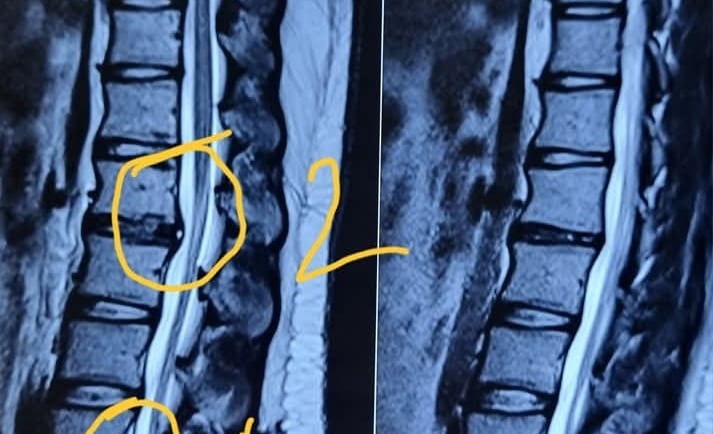

🍀 Diagnosis:

Diagnosis of disc prolapse typically involves a combination of medical history review, physical examination assessing reflexes and strength, and imaging studies such as MRI or CT scan to visualize the spine and confirm the location and severity of the prolapsed disc.